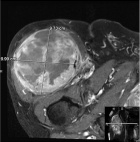

83 year old male with a two month history of a right thigh mass

Zoom image: Radiological image Radiological image.